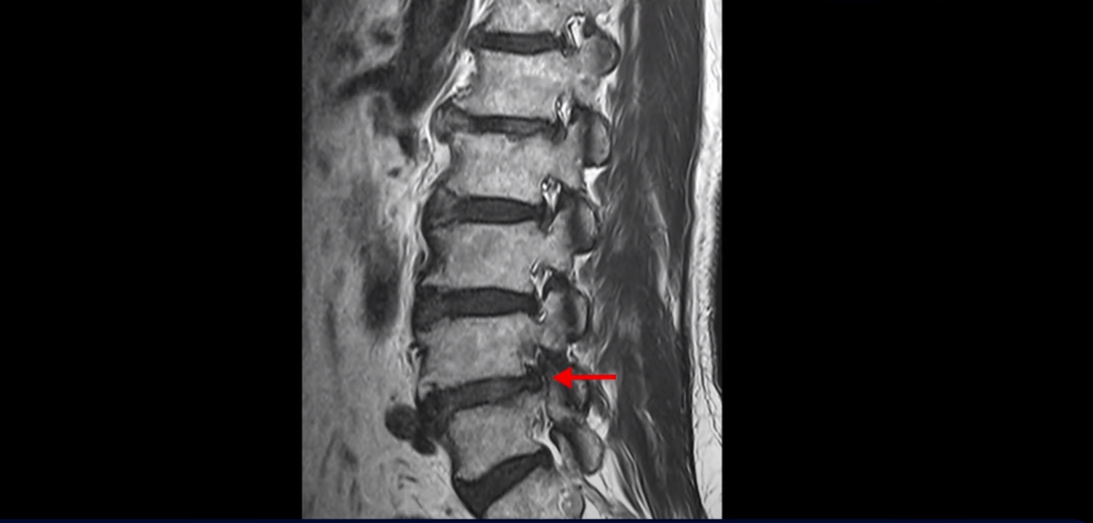

이분 MRI를 보면 척추의 여러 마디가 퇴행이 진행되어 안 좋습니다.

특히 4번 5번 마디가 제일 안 좋은데 보시다시피, 하얗게 보여야 될 신경이 거의 안 보일 정도로 척추관이 좁아져 있습니다.

이분은 허리도 아프지만 왼쪽 엉덩이와 다리가 너무 심하게 저리고 아팠는데 역시나 왼쪽 신경 가지가 빠져나가는 구멍이 막혀 있어서 매우 어둡게 보입니다.